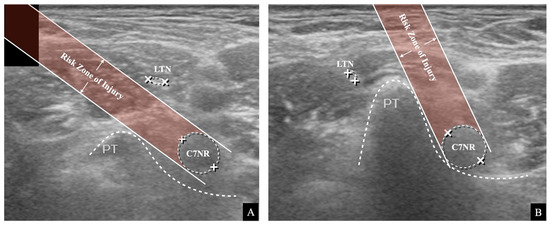

2.2. Simulated Risk Analysis of Long Thoracic Nerve Injury

indicates that it was outside the risk area in the simulated risk analysis. The LTN’s mean location and locational area estimated by the mean ± standard deviation (SD) are presented. The painted area indicates that the needle’s trajectory is expected to be associated with a high risk of LTN injury.